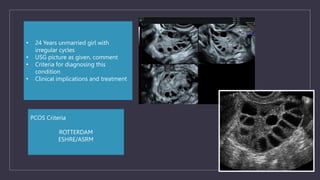

PCOS Criteria

ROTTERDAM

ESHRE/ASRM

• 24 Years unmarried girl with

irregular cycles

• USG picture as given, comment

• Criteria for diagnosing this

condition

• Clinical implications and treatment